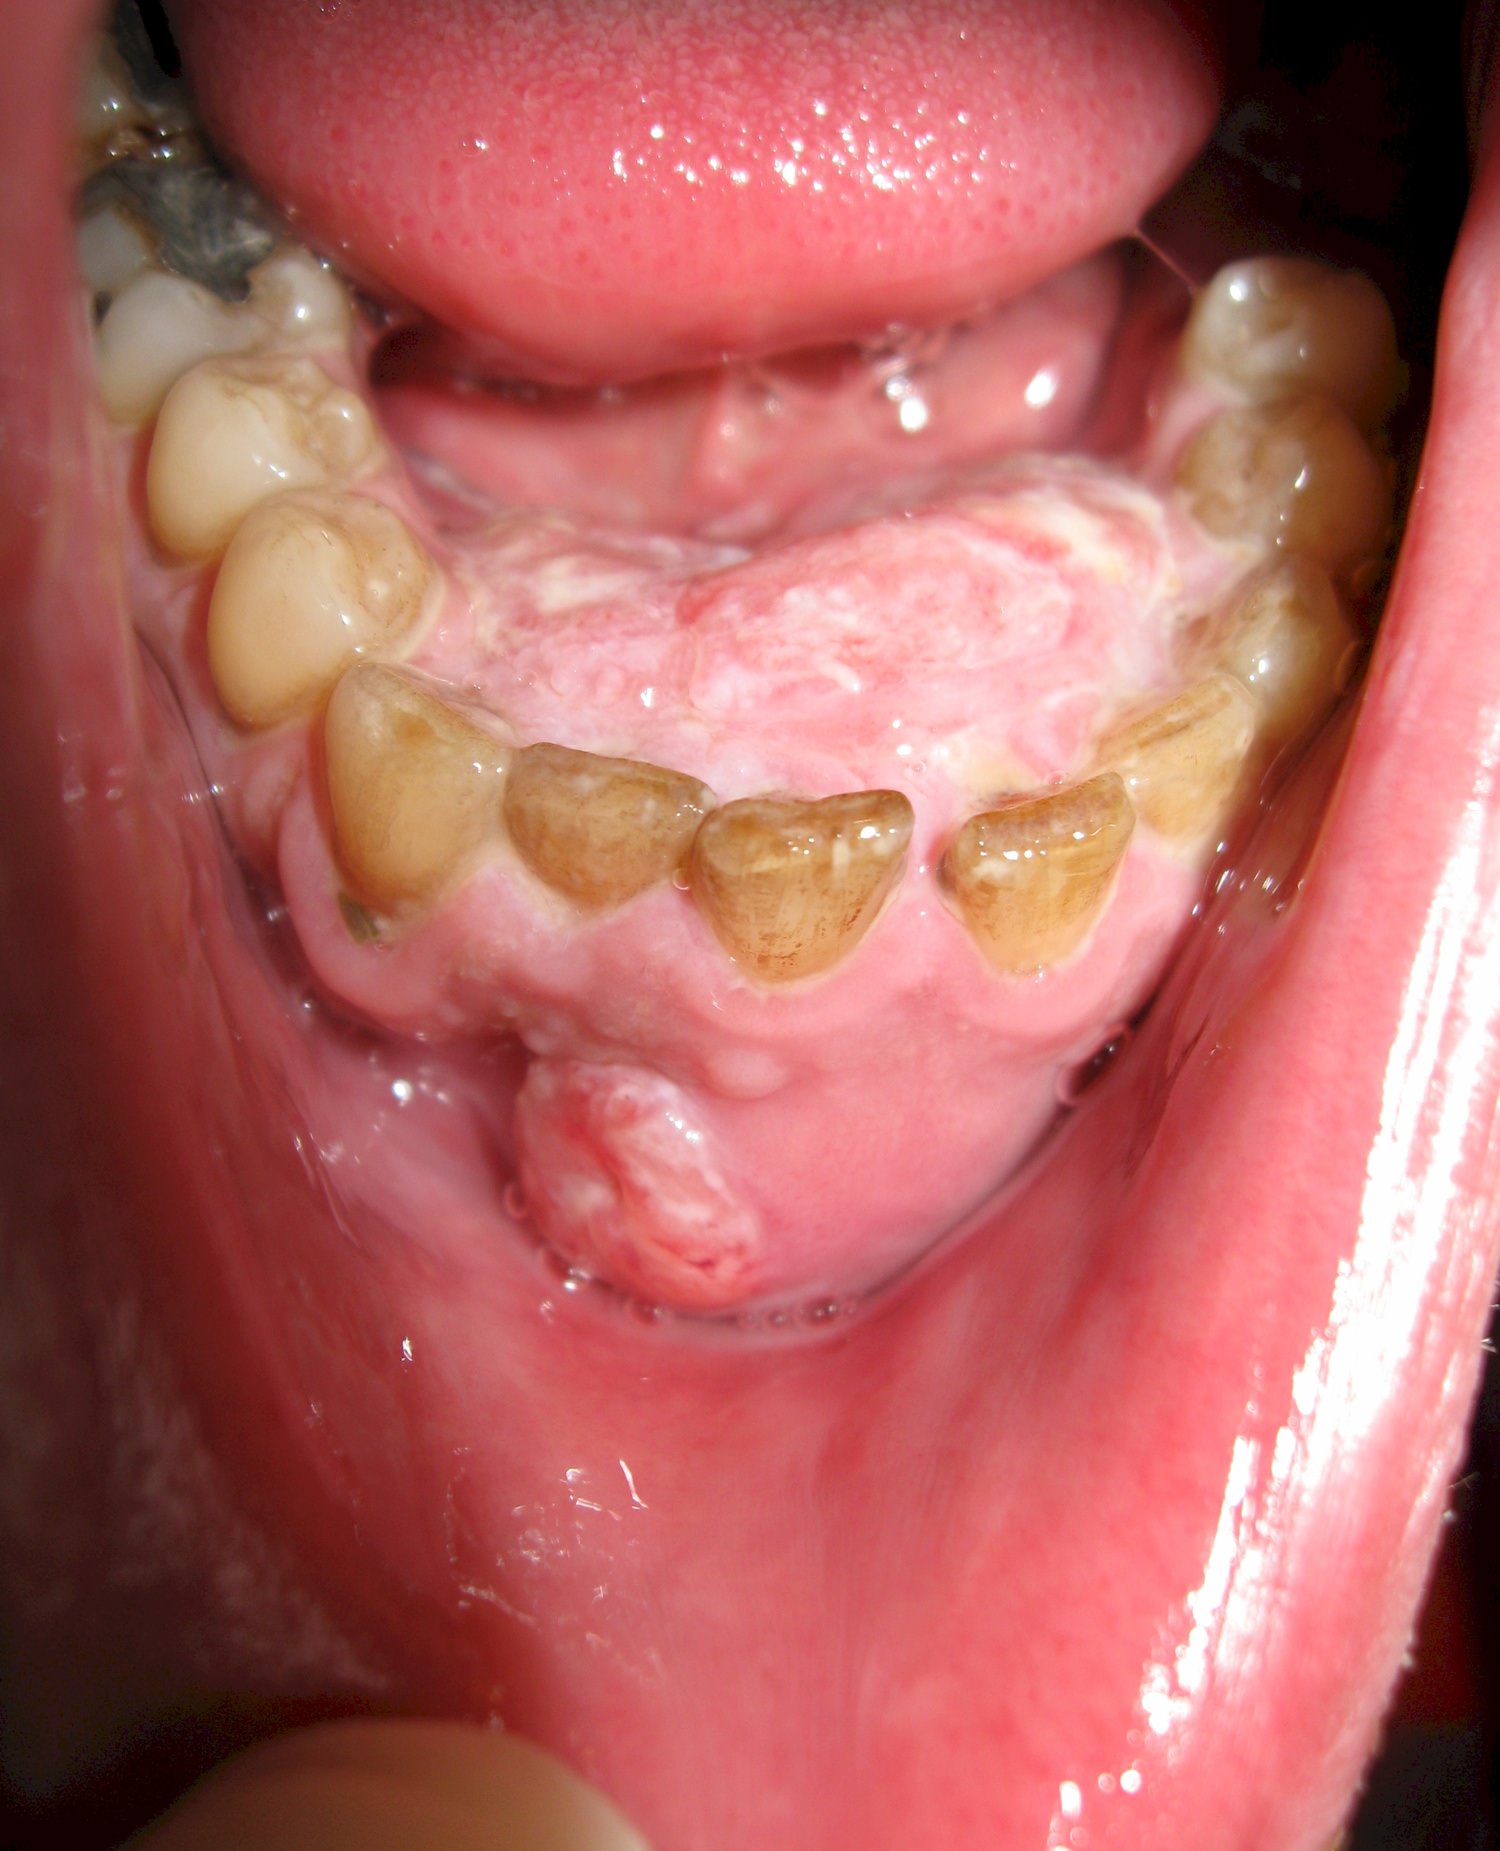

Рак ротовой полости